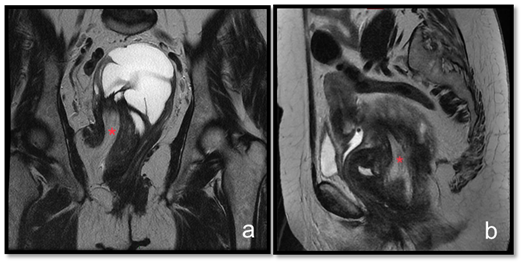

A 71-year-old woman developed clinically gluteal cellulitis. During the diagnostic investigation by transvaginal pelvic ultrasonography, a multiloculated pelvic solid and cystic lesion was detected, with septations and scarce blood flow to color Doppler (Figure 1). This exam couldn’t define the original site of this lesion. Pelvic magnetic resonance imaging (MRI) revealed a large pelvic solid and cystic formation with well-defined limits and an important cranial and anterior dislocation of the uterus and bladder (Figure 2). Retraction of the right ischiorectal fossa fat through the lesion and towards the pelvic cavity was detected (Figure 3) and represented a decisive information in the diagnostic investigation. Patient underwent surgical resection with complete excision of the tumor and evolved well in the postoperative (Figure 4). The histopathological examination revealed a neoplasm characterized by a densely collagenized stroma with alternating zones of cellularity, consisting of small spindled or ovoid cells with moderate amounts of eosinophilic cytoplasm and nuclei with fine chromatin and inconspicuous nucleoli, clustered around thin-walled capillaries (Figure 5). The immunohistochemical study revealed diffuse expression of desmin as well as estrogen and progesterone receptors, corroborating the diagnosis of angiomyofibroblastoma. There is no sign of tumor recurrence in periodic imaging exam less than one year after surgery.

Figure 3 T2 weighted MRI sequences at coronal (A) and sagittal (B) planes. Fat from the right ischiorectal region insinuates along the lesion to the pelvic region (red asteristic).